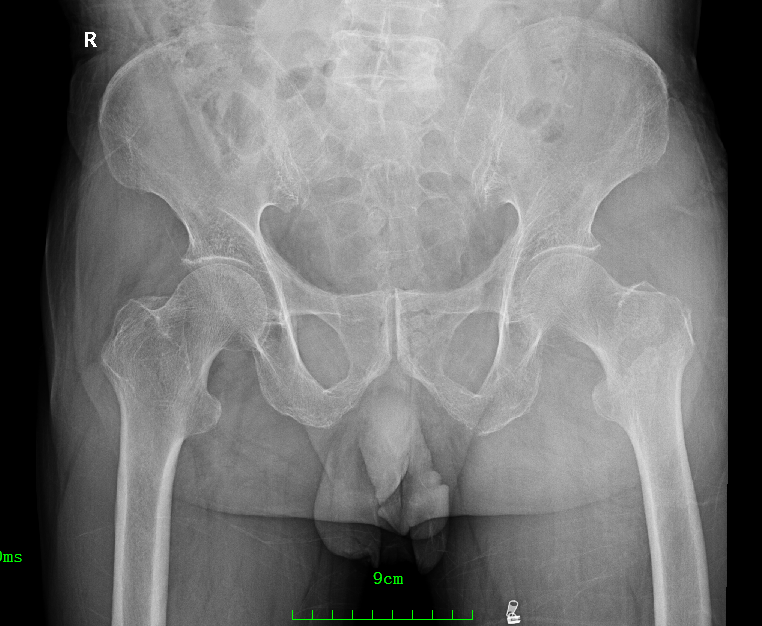

患 者:邱某,男,79岁。

主 诉:因撞伤致左髋部疼痛、活动受限30分钟,入院治疗。

症 见:患者自诉被小货车撞伤,致左髋部肿痛伴活动受限,受伤当时患者无昏迷、晕厥,无恶心、呕吐,无胸闷、气促,受伤后来入院就诊。

查 体:T:36.7℃,P:52次/分,R:20次/分,BP:130/74mmHg。

专科检查:神志清楚,检查合作,左髋部稍肿胀,皮肤粘膜完整,局部皮色淤青,左下肢外旋、未见明显短缩,左髋局部压痛,左足底叩击痛,左髋关节主动伸屈、外展、内收等活动受限;左下肢末梢皮色红润,感觉良好。

影像资料:

骨盆正位

髋部CT

髋部CT+骨三维

诊 断:

左股骨粗隆骨折,伴心动过缓,三度房室传导阻滞。阿托品试验阴性。